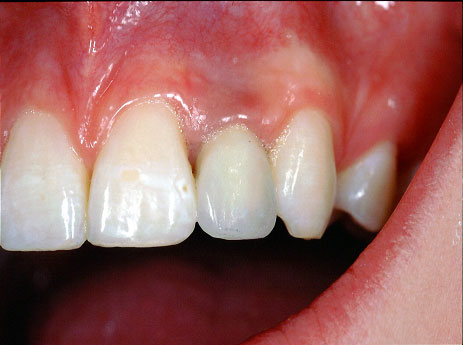

Einzelne Zähne können auch in völlig gesunden Gebissen durch Unfall oder Entzündungen verloren gehen, ebenso sind besonders die oberen seitlichen Schneidezähne häufiger nicht angelegt. Die drei Bilder zeigen den Ersatz eines nicht angelegten seitlichen oberen Schneidezahnes bei einem Jugendlichen.